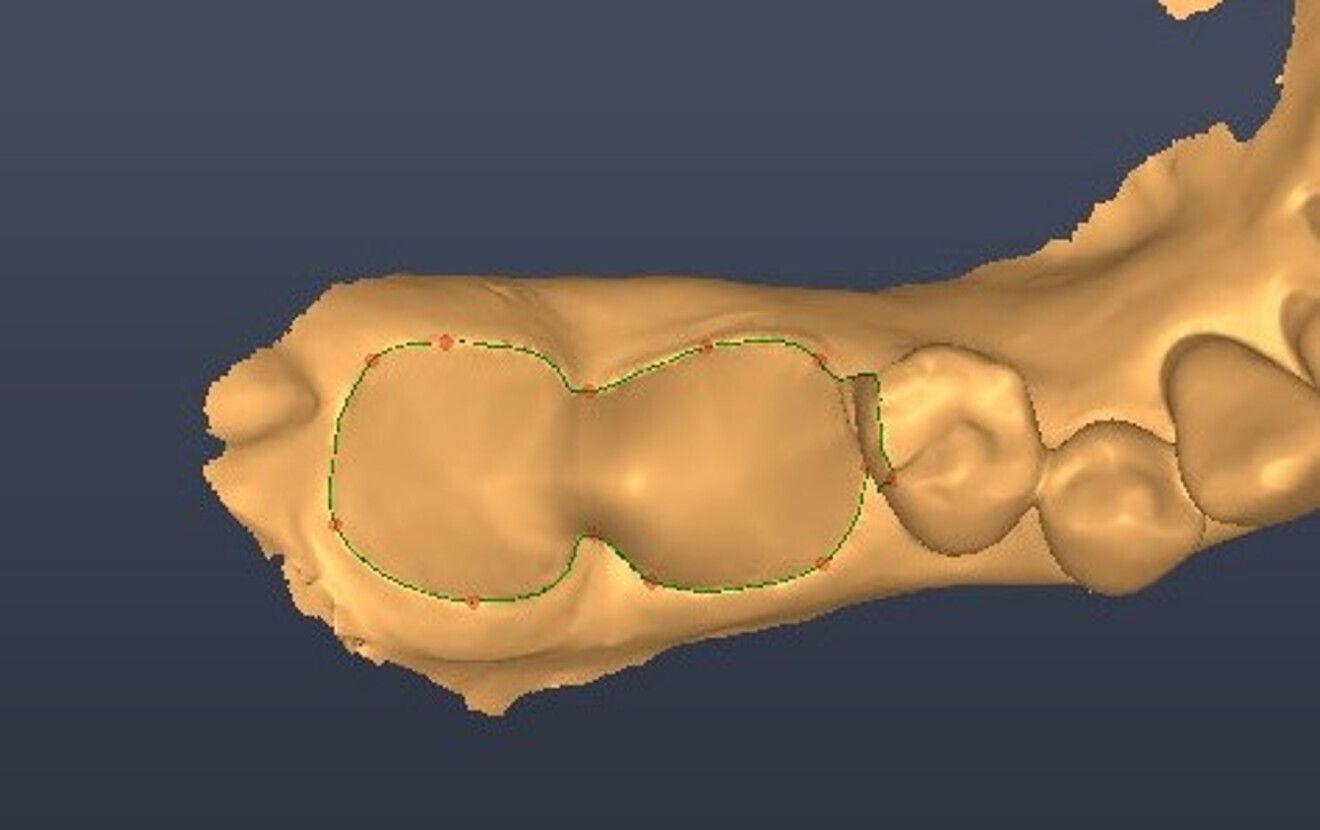

Fig. 3: Virtual extraction.

Fig. 4: Digital implant planning, occlusal view.

Fig. 5: Digital implant planning, labial view.